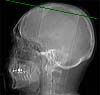

Radioanatomie TDM de l'encéphale avec injection

Sinus sagittal supérieur

Faux du cerveau